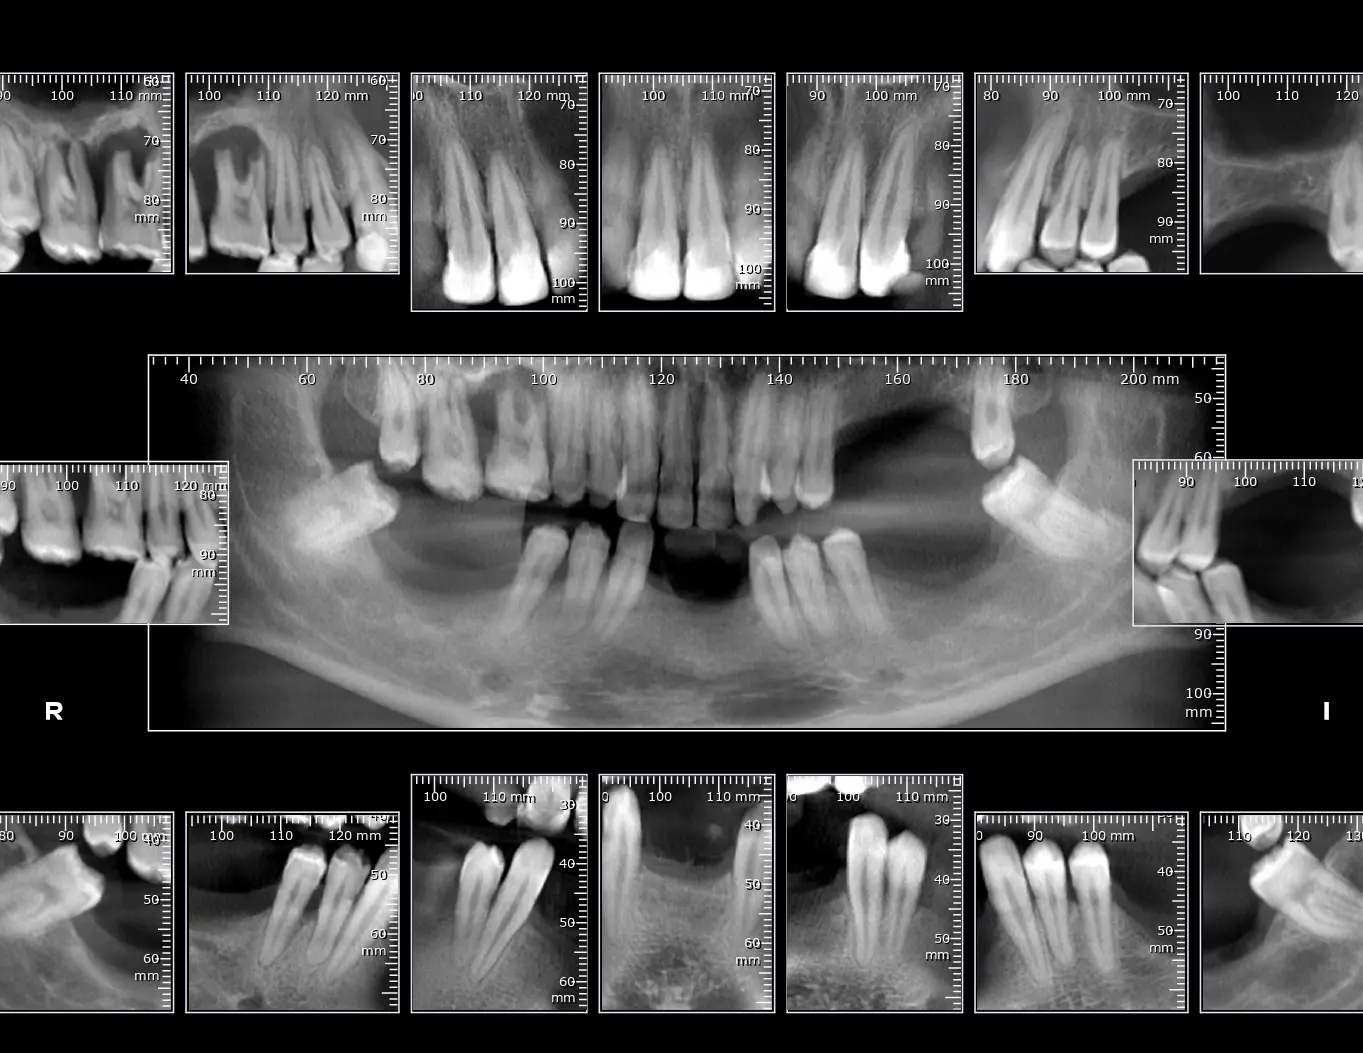

Estudio Periapical Completo.

Tomado con Tomógrafo consta de las 14 imágenes periapicales más aletas de mordida izquierda y derecha.

Radiografías Periapicales

Normalmente, se usan para obtener una imagen completa de la estructura de uno o dos dientes: raíces y coronas.

Una imagen detallada de uno o dos dientes, ideal para diagnosticar caries, enfermedades periodontales, fracturas dentales o movimientos dentales. Tamaño: 3.5 x 3.2 cm.

Aleta Mordible

La placa se coloca a lo largo de la mordida del paciente, para obtener una imagen completa de las coronas dentales del paciente. Se usan especialmente en los casos de caries interproximal. Captura una imagen de los dientes superiores e inferiores para detectar caries interproximales.

Tamaño: 3.5 x 3.2 cm. Perfecta para un diagnóstico claro y rápido.